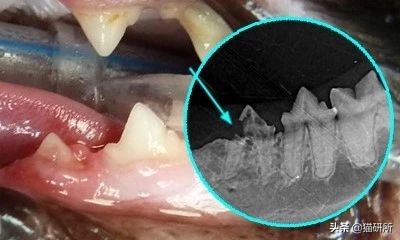

口腔X线检查

用于评估根尖、牙周病及提示肿瘤的骨吸收

2014年发表的一项对2002年到2012年的猫慢性口龈炎(FCGS)的X线结果的统计显示,患FCGS的猫,更容易出现:外部炎性齿根吸收、根尖滞留、齿槽骨吸收(特别是水平骨)。

图自DeBowes L J, DuPont G A